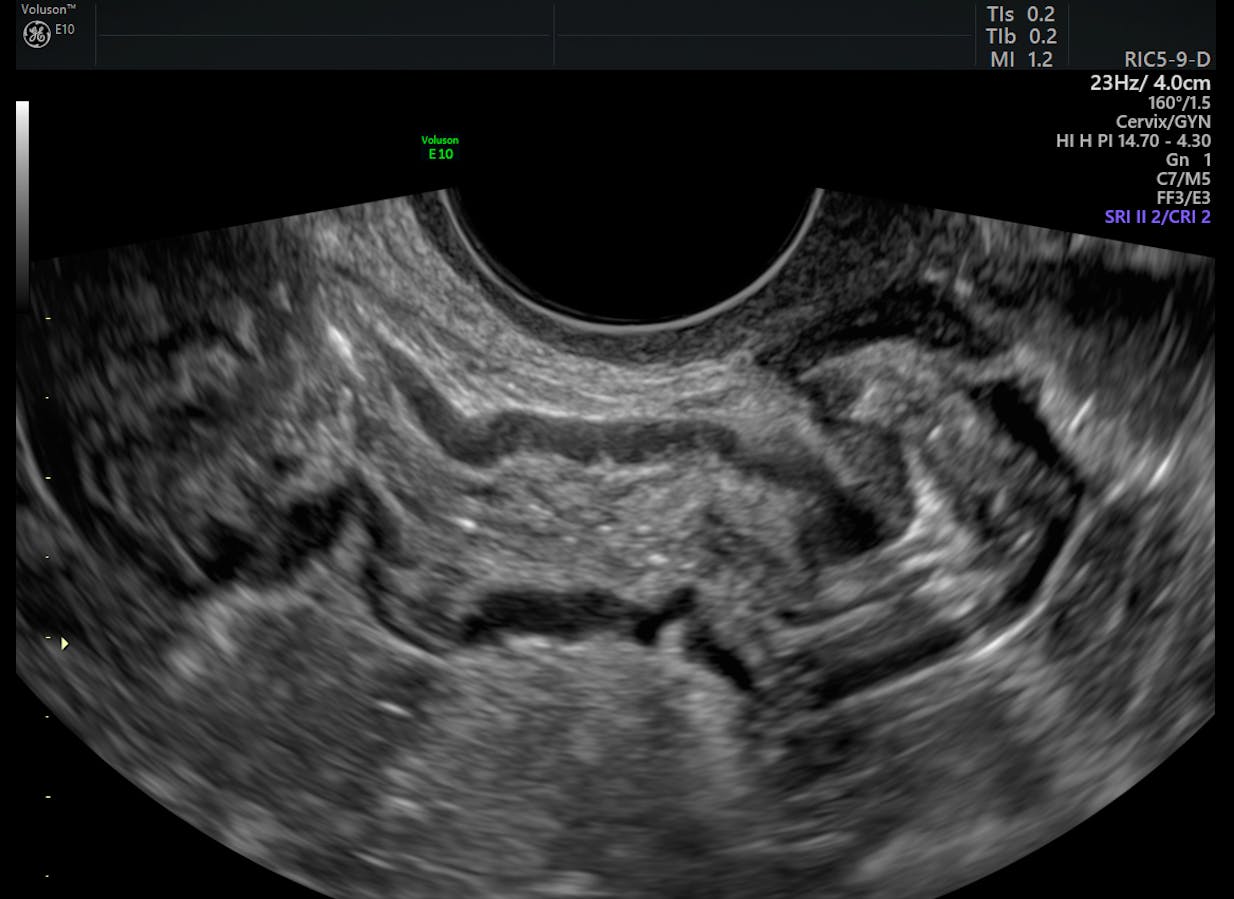

Deeply infiltrative endometriosis lesion of the bowel on ...

Deeply infiltrative endometriosis lesion of the bowel on ... from www.researchgate.net